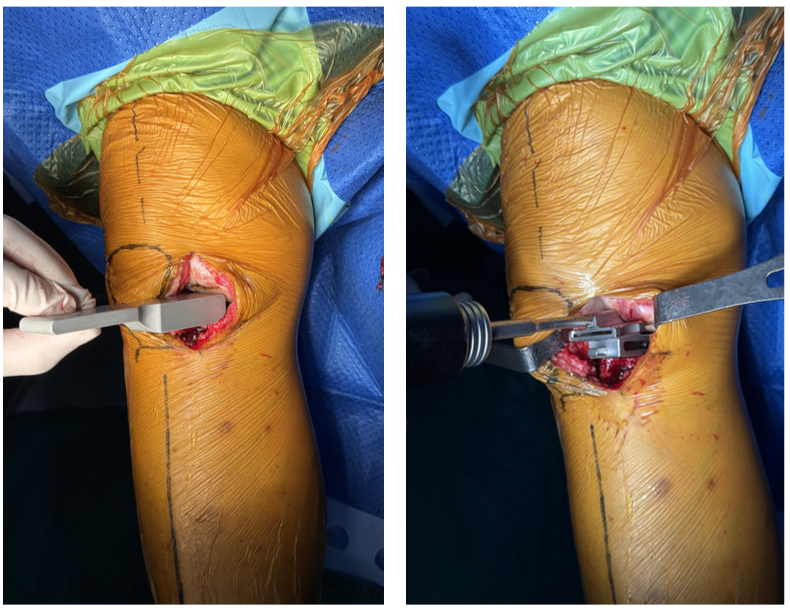

三、手术视频